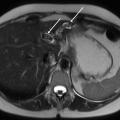

Échographie hépatique : examen clé du diagnostic

L’échographie hépatique est l’examen clé pour le diagnostic de syndrome LPAC. Celle-ci met typiquement en évidence les signes d’une microlithiase intrahépatique sous la forme d’images en « queue de comète » (échos de répétition liés à la vibration des microcristaux sous le faisceau d’ultrasons), de micro-­spots ou de « boue biliaire » (sludge) le long des canaux intrahépatiques (fig. 1A). Ces signes sont parfois difficilement identifiables, notamment en situation non sensibilisée et pour un opérateur non entraîné. Le principal diagnostic différentiel est représenté par les microhamartomes (ou complexes de von Meyenburg) qui peuvent parfois se présenter sous la forme d’artéfacts en queue de comète.9 Une échographie normale standard n’élimine pas le diag­nostic et il peut être nécessaire de répéter l’examen par un radiologue expérimenté et formé à la sémio­logie du syndrome LPAC. Moins fréquemment (5 à 10 % des cas), le syndrome LPAC peut se présenter sous la forme de vrais calculs (macrolithiases) intra- ou extrahépatiques (fig. 1B).4 Une lithiase vésiculaire n’est observée que chez un tiers des patients atteints de syndrome LPAC.